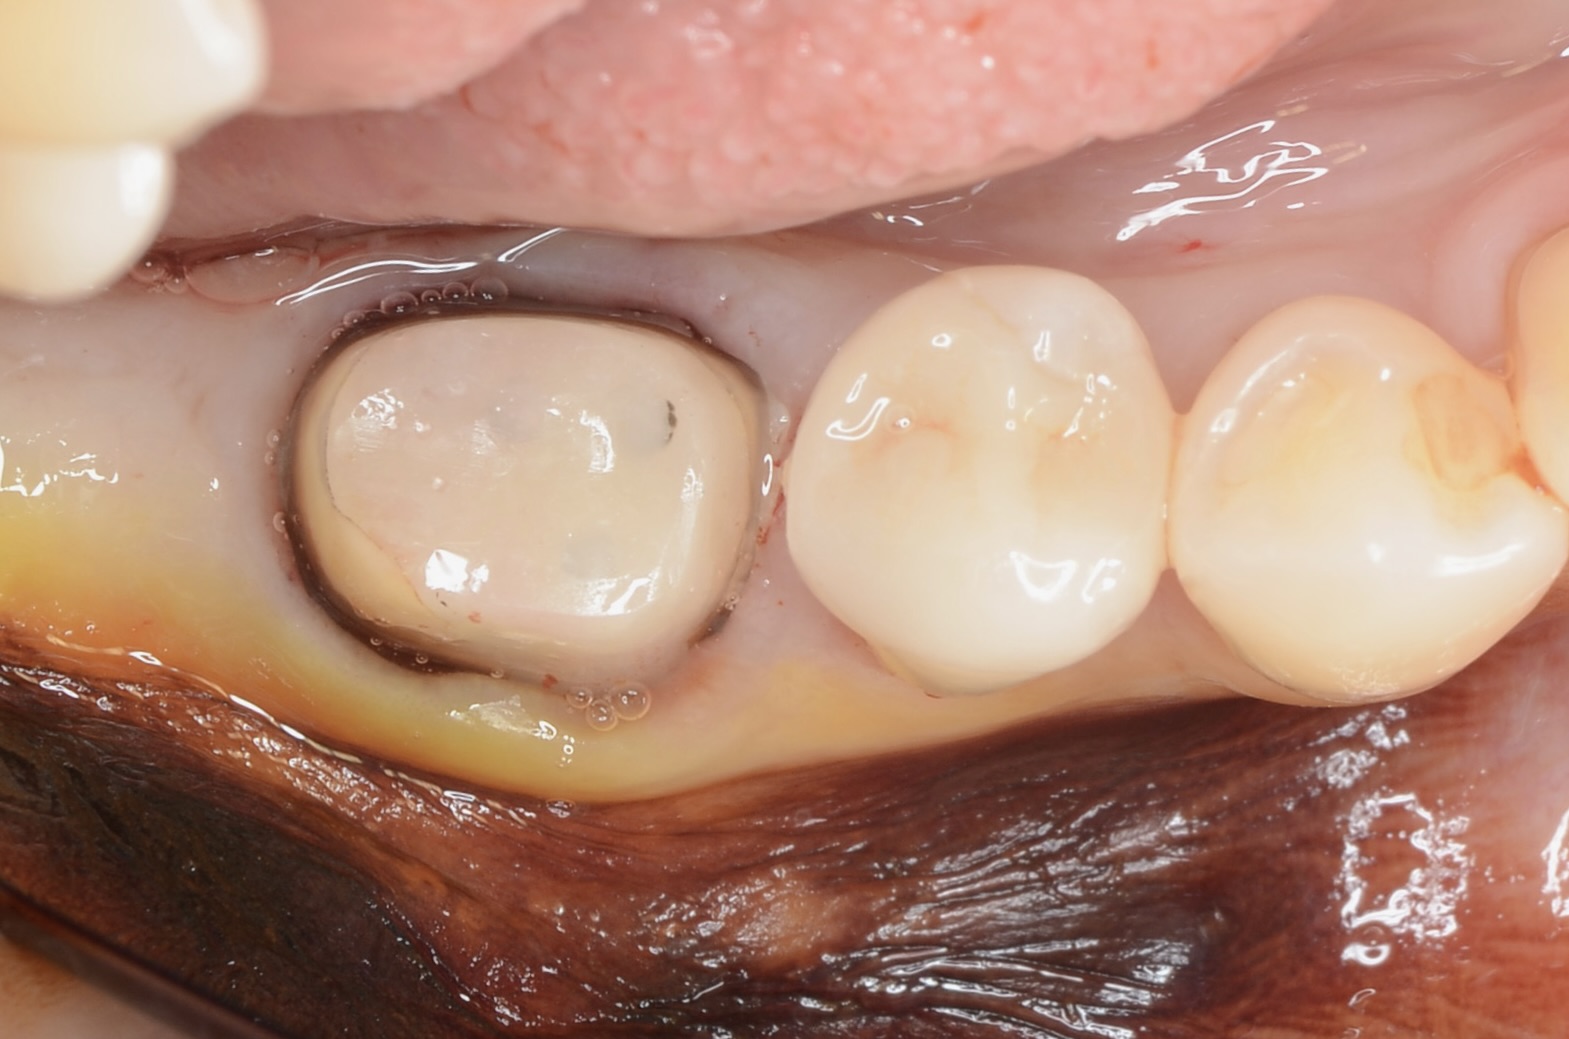

レジンコア除去後

歯頸部の歯肉縁下にまで虫歯が広がっていました。 通常であれば、抜歯になります。 -